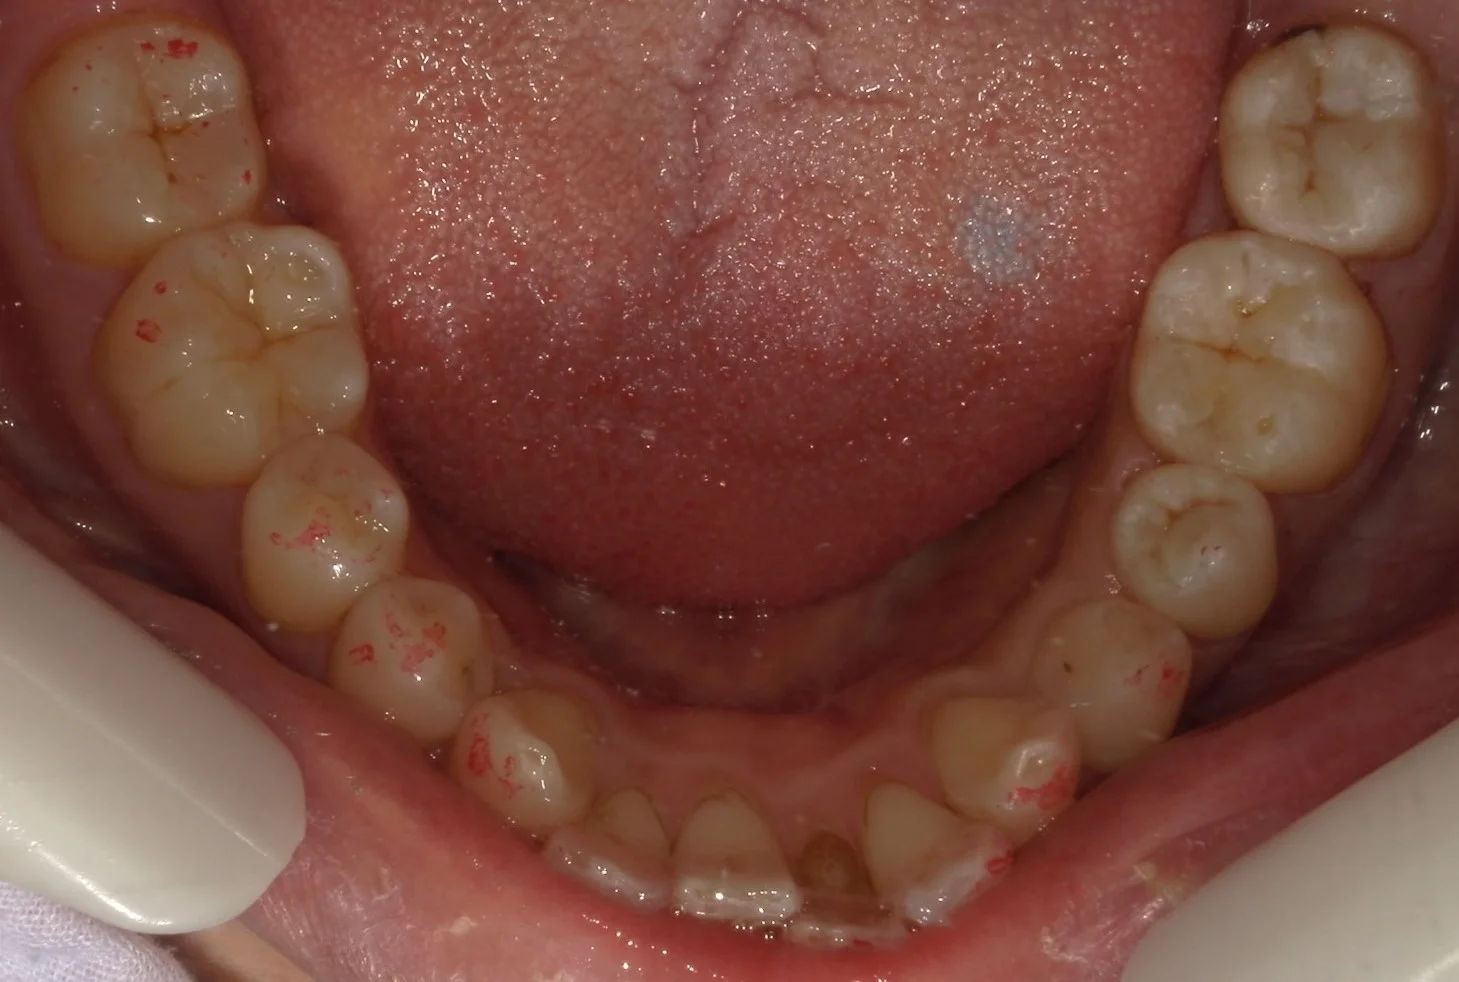

まずは術前です。

今回行ったのは、画面上で右側3つの歯です。

奥二つの金属の詰め物の下に虫歯があったのと・・・

3~4カ月ほど前に他院にて治療されたセラミックInの適合が悪かったためです。